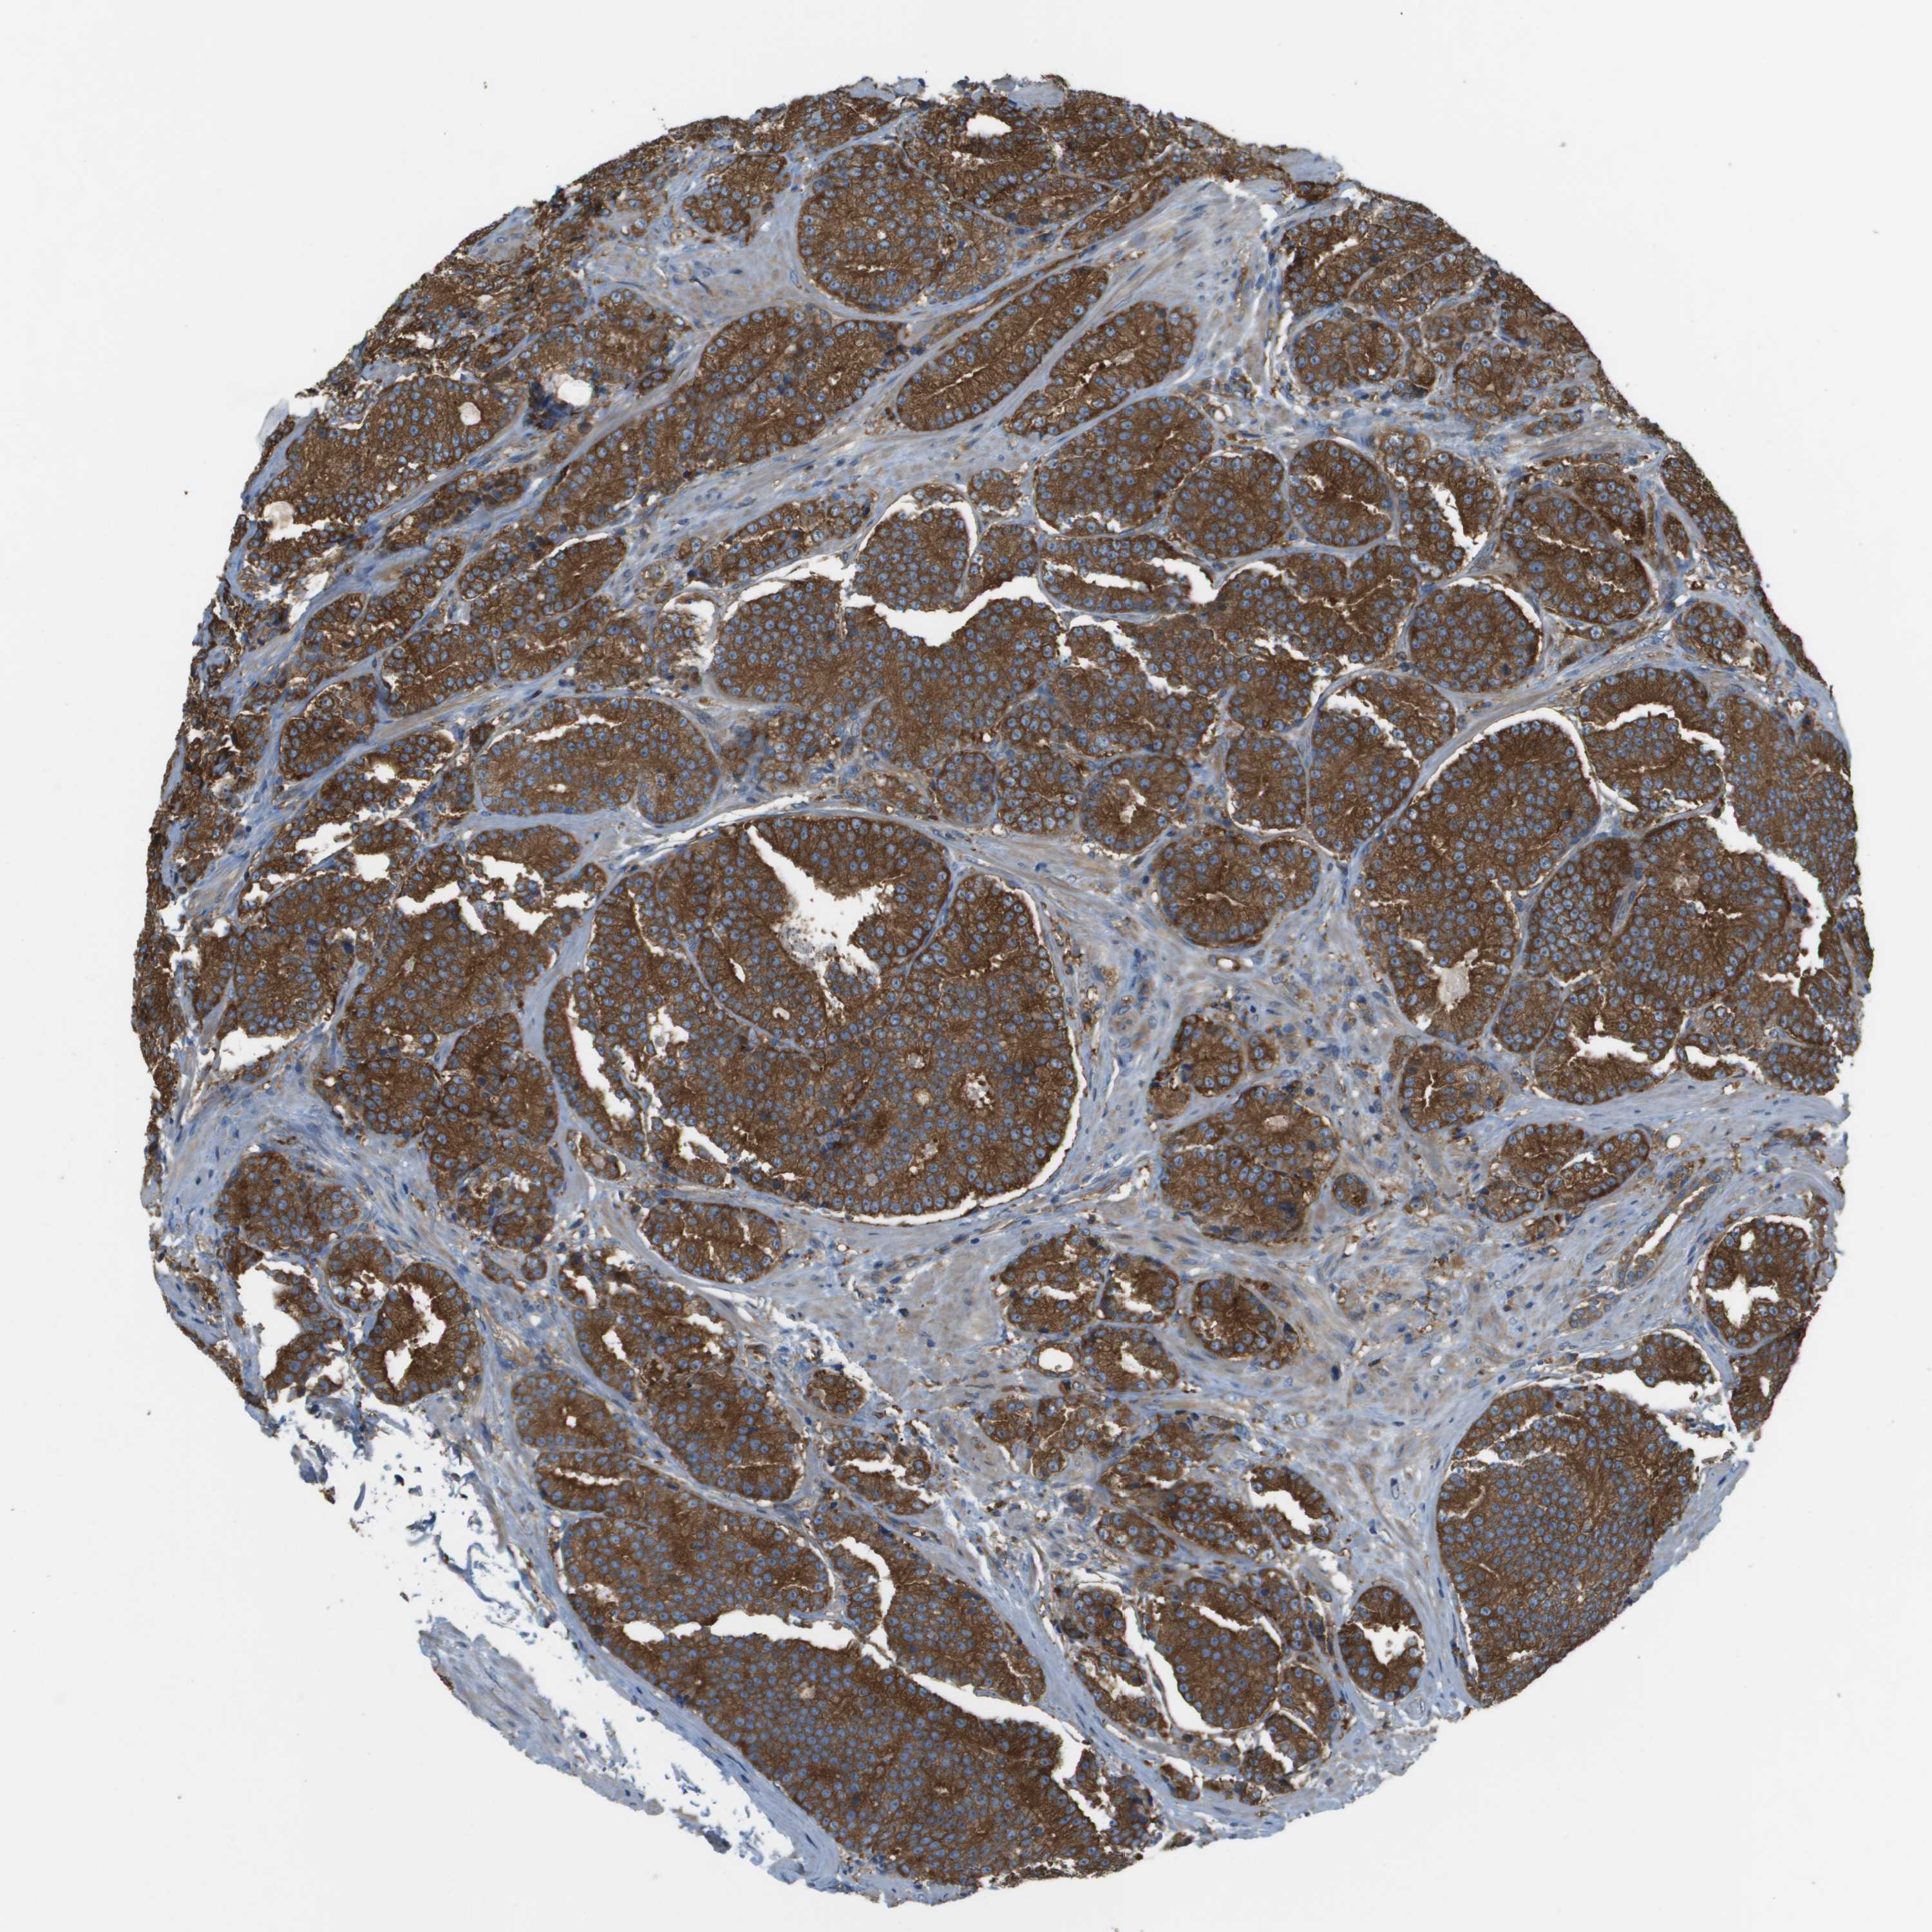

PROSTATE CANCER - Protein expressioni

A mouse-over function shows sample information and annotation data. Click on an image to view it in a full screen mode. Samples can be filtered based on level of antibody staining by selecting one or several of the following categories: high, medium, low and not detected. The assay and annotation is described here.

Note that samples used for immunohistochemistry by the Human Protein Atlas do not correspond to samples in the TCGA dataset.

Antibody stainingi

Antibody staining in the annotated cell types in the current human tissue is reported as not detected, low, medium, or high, based on conventional immunohistochemistry profiling in selected tissues. This score is based on the combination of the staining intensity and fraction of stained cells.

Each image is clickable and will lead to virtual microscopy that enables deeper exploration of all samples and also displays staining intensity scores, fraction scores and subcellular localization as well as patient and tissue information for each sample.

Antibody HPA070456

Antibody CAB017616

Staining

High

Medium

Low

Not detected

Intensity

Strong

Moderate

Weak

Negative

Quantity

>75%

75%-25%

<25%

None

Location

Nuclear

Cytoplasmic/membranous

Cytoplasmic/membranous,nuclear

Adenocarcinoma, High grade

Adenocarcinoma, NOS

Adenocarcinoma, Low grade